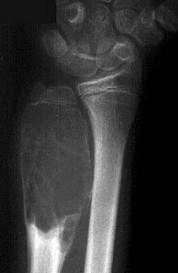

问题 男性,17岁,近2年来感右前臂疼痛,肿胀,2周前由于疼痛加剧,查体右前臂压痛明显,皮肤稍显红肿,请结合所提供图像,选择最佳选项()

选项 A.骨囊肿 B.巨骨细胞瘤 C.动脉瘤样骨囊肿 D.软骨瘤 E.骨血管球瘤

答案 C